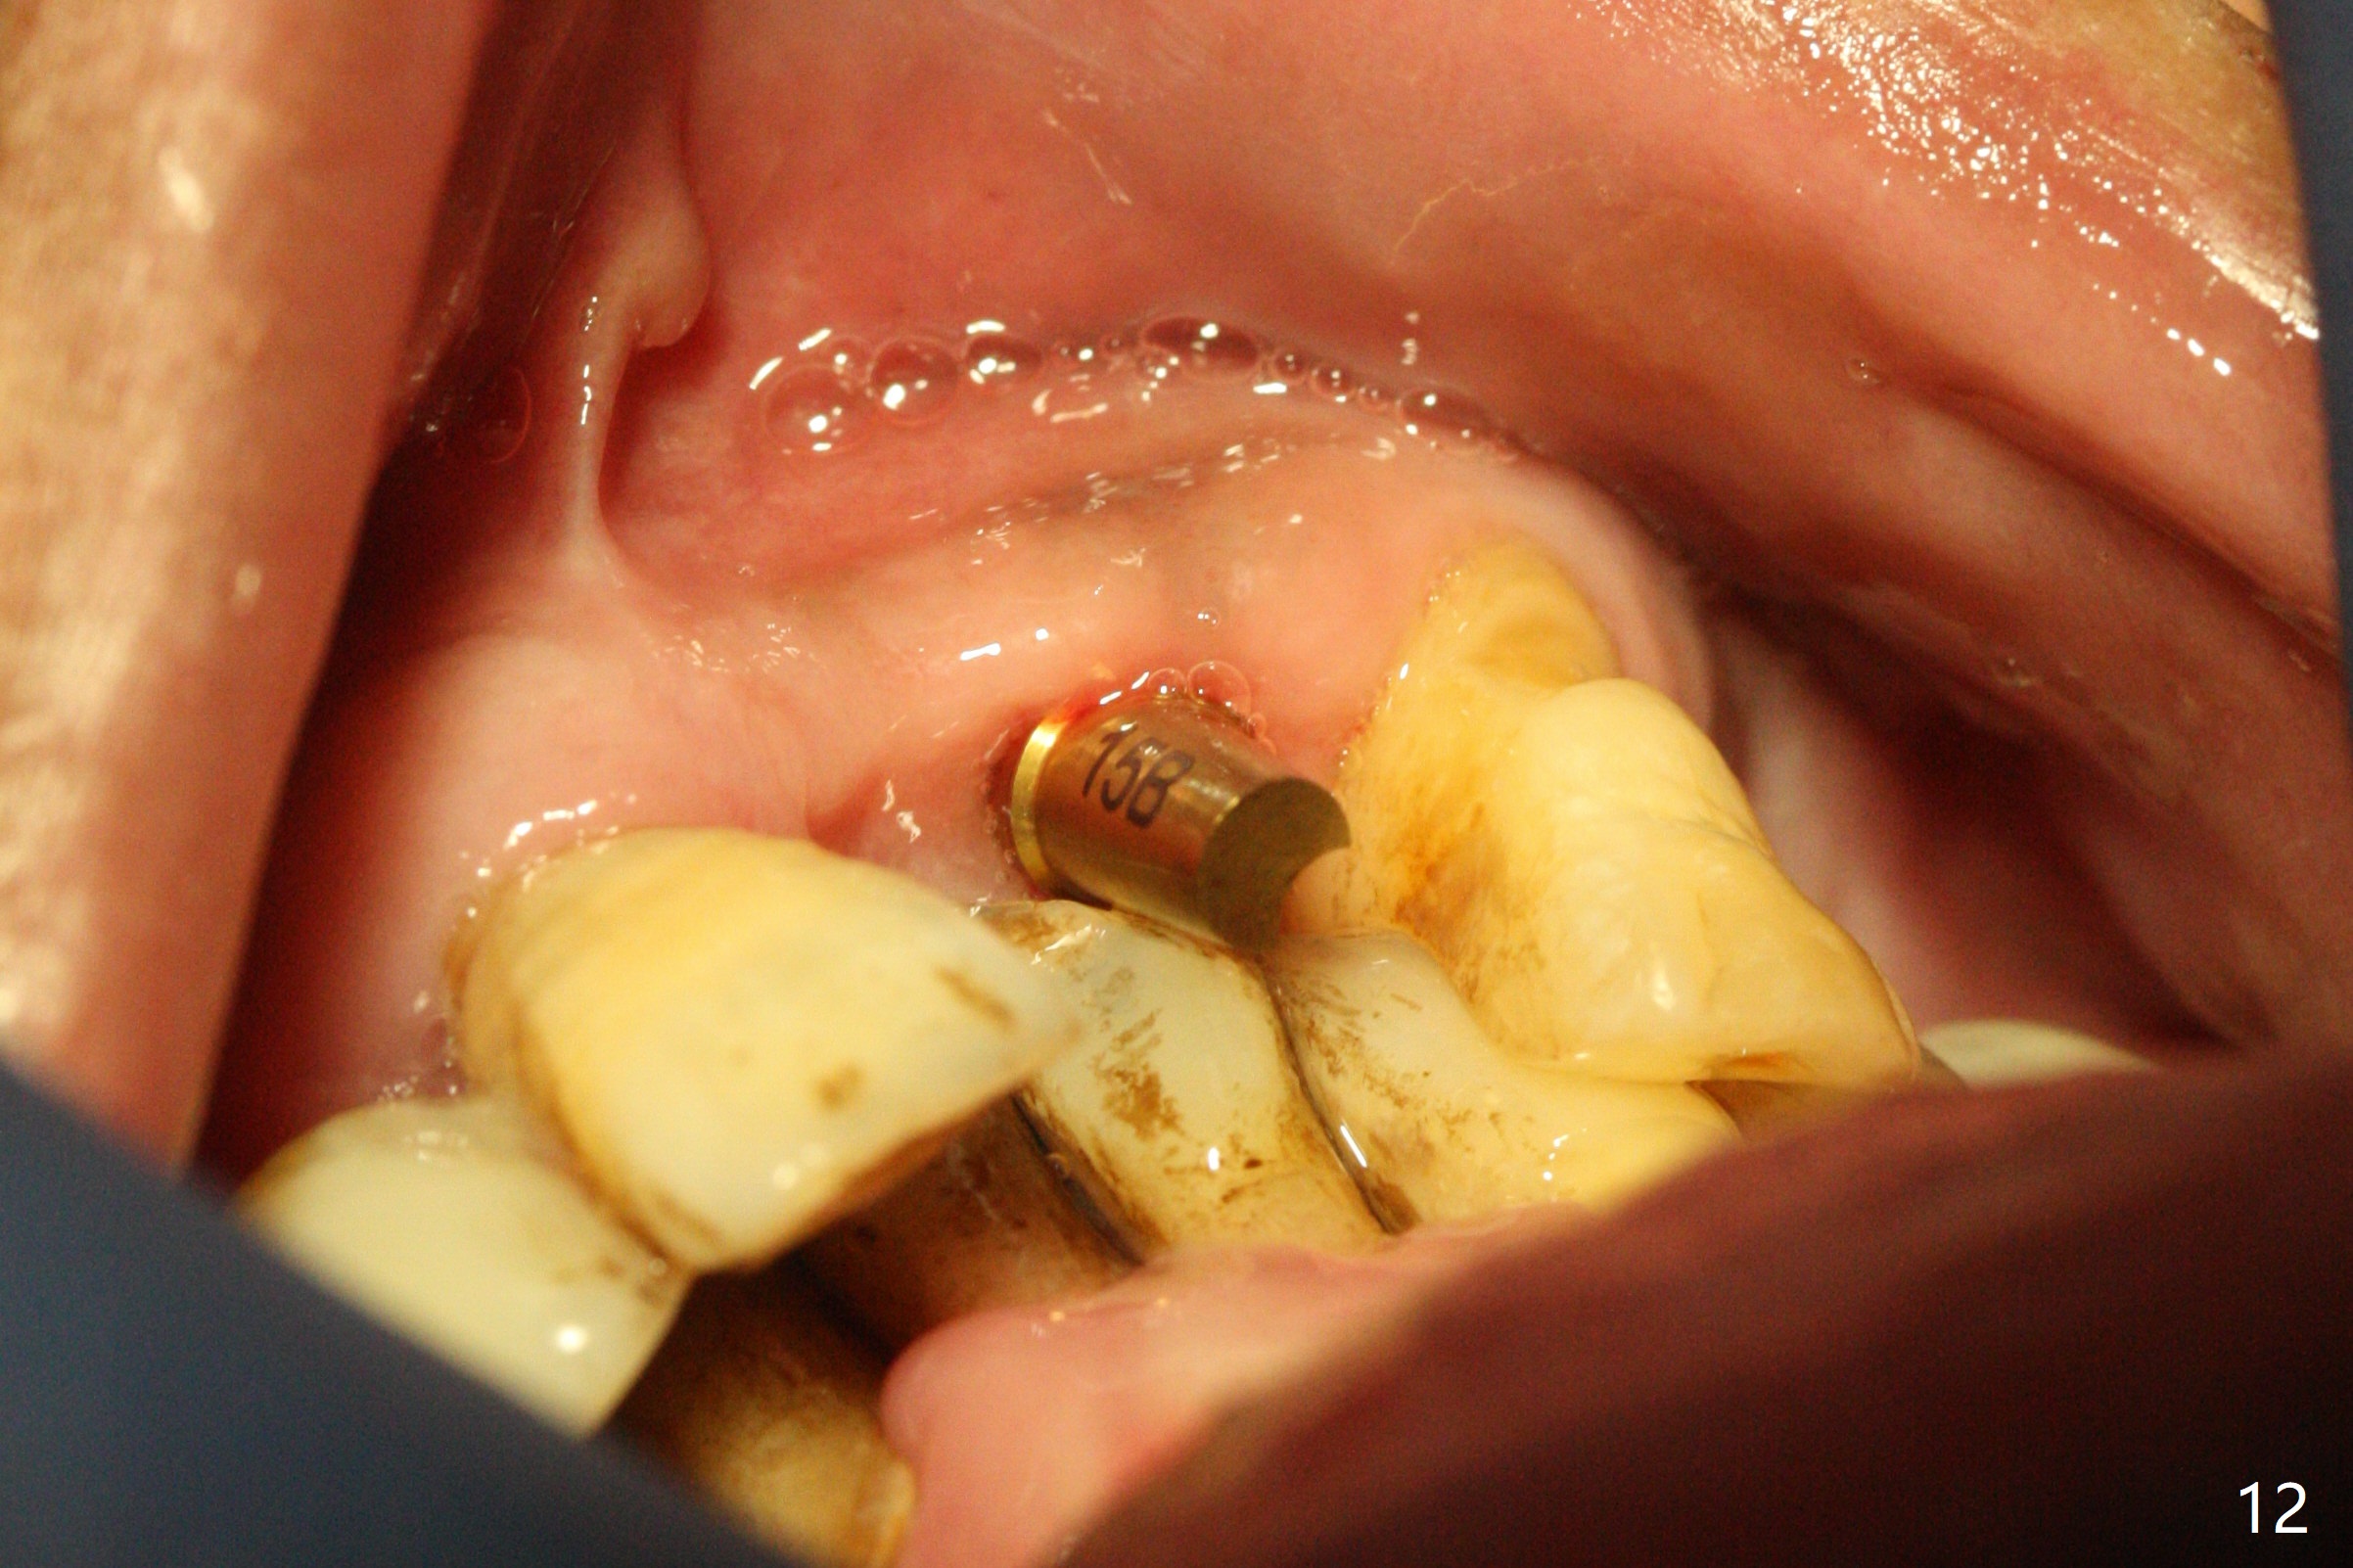

After a 4x10 mm implant is placed with fixture mounting (Fig.2 M) following sinus lift (*) at #12, osteotomy is initiated at #10 (Fig.1 (T: tube of surgical guide)). It appears that the drill (D) has good trajectory (between the Incisive Canal (red dashed line) and the canine root). The final position of the implant at #10 is acceptable (Fig.3). The implant at #12 is placed deeper (Fig.4 (arrow), as compared to Fig.2) because of clinically buccal superficial placement. The most critical challenge is anterior deep bite associated with posterior collapse. Periodontal dressing is applied. When the latter dislodges, there is minimal clearance for a provisional. Periodontal dressing is re-applied. The patient (smoker, partial edentulism with occlusal interference) returns for provisional nearly 1 month postop with chief complaint "something is lost in the back". In fact the healing abutment at #12 is lost with buccal granulation tissue (Fig.5). When a new abutment is seated, there is discomfort. When a healing screw is placed, it cannot be seated completely with two separate trials (Fig.6,7). Should we leave it as it is or open up for complete seating? It appears that the implant is loose. After preparation for clearance at #10, the abutment is retightened. It appears to turn with the underlying implant with discomfort. A 4x5 mm healing abutment is placed to reduce micro-movement. One week later, the infection at #12 dissolves with oral Amoxicillin (Fig.8). Due to limited occlusal clearance and implant tenderness when the abutment abutment is retightened, the cemented abutment is changed to a healing abutment. The implant at #10 seems to be osteointegrated, while the healing screw at #12 remains incomplete seating 3 months postop (Fig.9). The loose healing screw cannot be retightened securely, as there is bone loss around the implant 3 months postop (Fig.10 *). When a 4.5 mm x 15 degree 4 mm cuff angled abutment is placed, the mesiodistal trajectory improves (Fig.11), but there is no occlusal clearance (Fig.12). The latter would form when posterior support is established (Fig.13, either removable appliance (which the patient hates) or fixed one (finance)). Fig.14 shows the unhealed site of #12. Incision confirms the bone loss around the implant, which is removed. Although the sinus floor is absent, there is no membrane perforation. After debridement, allograft mixed with small amount of Osteogen is placed (Fig.15,16 G) and covered with Osteogen plug and 6-month membrane.